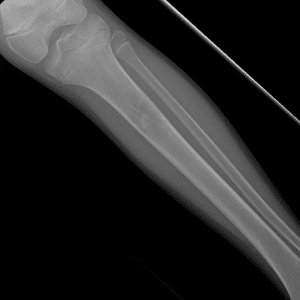

Pediatric Radiographs